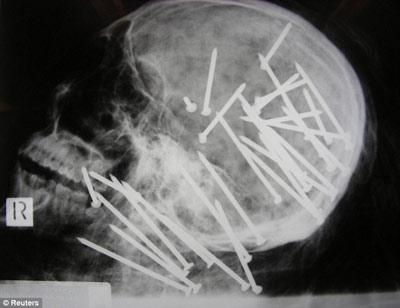

X光顯示,劉晨(音譯)頭部和頸部被釘有30枚鋼釘

據(jù)報(bào)道,該男子名叫劉晨(音譯),于2000年移民澳大利亞墨爾本市,4年后搬往悉尼。2008年11月,劉晨的男性友人向悉尼警方報(bào)案,稱其已經(jīng)失蹤一段時(shí)間,警方遂展開調(diào)查。兩周后,兩名在悉尼喬治河上劃船的男孩發(fā)現(xiàn)了劉晨已經(jīng)高度腐爛的浮尸。警方稱,當(dāng)時(shí)劉晨被一條毯子緊裹著,四肢被電線捆得結(jié)結(jié)實(shí)實(shí),警方將尸體交與法醫(yī)進(jìn)行X光檢查后驚異地在他頭部和頸部發(fā)現(xiàn)了30枚鋼釘。

負(fù)責(zé)本案的警官馬克·紐漢表示:“尸檢結(jié)果顯示,兇手用一種無繩氣動(dòng)式射釘槍對著死者的頭部和頸部開了30槍,這種標(biāo)準(zhǔn)式射釘槍哪都可以買到。”悉尼警司杰夫·貝雷斯福德告訴記者:“這起謀殺案令所有的警察震驚不已,在我36年的辦案生涯中,還從來沒見過性質(zhì)如此惡劣的兇案……就是因?yàn)檫@起謀殺案是如此的殘忍,所以我們希望公眾能夠?yàn)榫教峁└嗟钠瓢妇€索。”